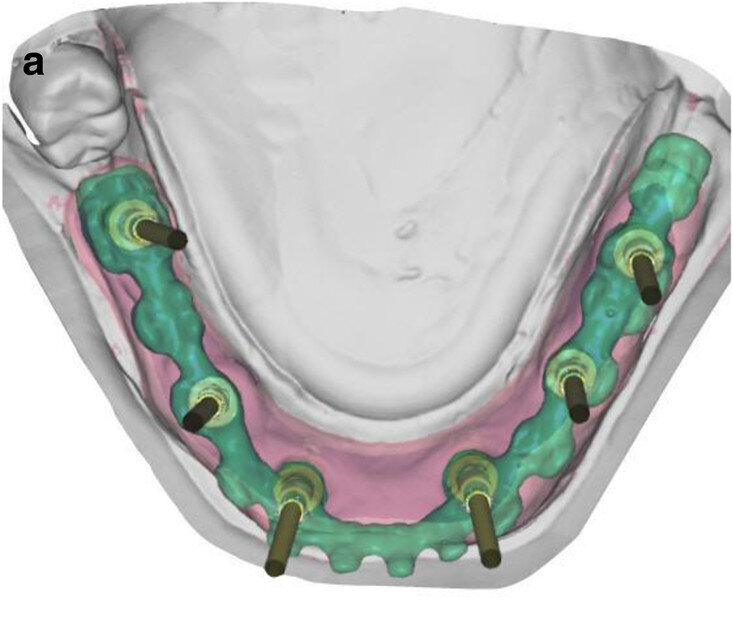

Fig. 5a: CAD/

CAM-fabricated surgical guides: tooth- and mucosa- supported (a) and implant- and mucosa-supported (b).

After extraction of the painful and extremely mobile teeth #41, 31 and 32 and adaptation of the existing RPD, a cone beam computed tomography scan (PaX-Uni3D, VATECH) with a 5 x 8 cm field of view, 85 kVp generator voltage, 5.5 mA generator current and 0.2 mm voxel size was performed to proceed with the detailed implant planning (Fig. 4). Based on the anatomical conditions and prosthetic planning (i.e. tooth set-up for the provisional RPD), six implants were virtually planned (3Diagnosys, 3DIEMME) in positions #46, 44, 42, 33, 35 and 36. As the implant positions #42 and 33 interfered with teeth #43 and 33, a two-step procedure with two surgical templates was planned for the guided implant placement (Figs. 5a & b). The templates were fabricated stereolithographically (DS3000 and XFAB, DWS) according to the virtual implant planning. Based on the same digital file (Figs. 6a–c), a provisional fixed dental prosthesis (FDP) was prepared preoperatively, allowing for an intra-oral adaptation between the abutments and the framework in order to achieve a passive fit (Figs. 7a–d).

The use of CAI software in the preoperative virtual 3D implant planning allowed for guided and immediate implant placement, and proved to be especially beneficial in the mandibular full-arch case presented. While there are some studies that have investigated outcomes of immediately loaded implants placed in edentulous patients using computer-aided, template-guided surgery to support an FDP,[25] only few case reports are available in the literature that describe the entire workflow, the patient’s state in detail and the usage of guided surgery templates with subsequent immediate loading.[3, 4] The considerably more complex combination of immediate implant placement and immediate loading required a high level of organisation between the implantologist and technician, minimising the required compliance of the patient. Pozzi et al. reported excellent results with CAD/CAM crossarch zirconia bridges on immediately loaded implants placed with computer-aided, template-guided surgery.[26] Several investigators have presented analyses of recent studies in this context, elaborating on the factors that influence accurate implant placement but also the comparable outcome of the restorations after guided implant placement.[15, 20, 21, 27–31] In the present case report, two CAD/CAM surgical templates were combined in this partially dentate patient, with extraction of teeth #42 and 33 and immediate implants performed in a sequenced order. The first scanner-based template was tooth- and mucosa-supported, enabling a higher template stability and thus more accurate guided osteotomies and implant placement. Four posterior implants were placed with this approach, allowing support of the second surgical template after extraction of teeth #42 and 33. The stability on these four points was high, as the implants in positions #42 and 33 showed a torque value of 35–40 Ncm each. The placement of the subsequent two anterior immediate implants was thus perfectly guided.